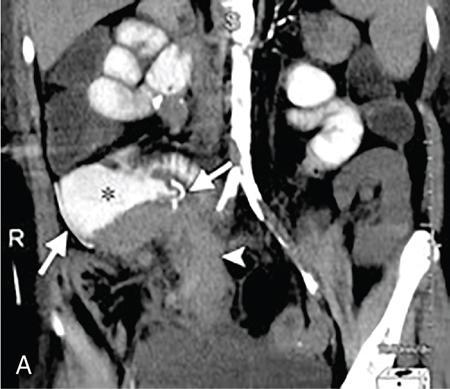

Kajal Patel, L. Murali Krishna Pancreatic transplantation is currently the only effective treatment for type 1 diabetes mellitus (93% of cases) allowing long-term glycaemic control without exogenous insulin injections. Additionally, it also counteracts the complications of diabetes mellitus, including diabetic neuropathy, retinopathy, vasculopathy and end-stage renal failure. The standard procedure is transplantation of a whole-organ cadaveric pancreas but less-invasive approaches such as islet cell transplantation are in development. Simultaneous pancreas–kidney (SPK) transplantation (78%) is done in most of the cases with same donor. In 16% cases, pancreas transplant can be done after kidney transplant also. But rarely, isolated pancreatic transplant (6%) can be done. The first pancreatic transplantation was performed in 1966 by the team of Dr. Kelly, Dr. Lillehei, Dr. Merkel, Dr. Idezuki Y and Dr. Goetz, 3 years after the first kidney transplantation. According to Scientific Registry of the United Network for Organ Sharing (UNOS) and the International Pancreas Transplant Registry (IPTR), the national 1-year patient, kidney and pancreas survival rates for recipients of an SPK transplant are 95%, 89% and 85%, respectively. Pancreas grafts have vascular and enteric connections that vary in their anatomic approach and understanding of this is critical for imaging. Imaging techniques are directed to display the pancreatic transplant arterial and venous vasculature, parenchyma and intestinal drainage pathway. Various surgical techniques have evolved over the years especially in the recent decade. Imaging of these patients should also be done based in the common surgical techniques and complications that arise of these surgeries. Though multiple modalities like ultrasonography (US), computed tomography (CT) and magnetic resonance (MR) imaging, radionuclide study and digital subtraction angiography (DSA) are available, each of them have their own advantages and limitations and usually a multimodality approach is required to diagnose the spectrum of complications. Preoperative evaluation typically considers the potential recipient’s age and ability to survive the operation. A relative contra-indication is the patient’s age (>55 years), due to the fact that the success rate is superior in younger individuals. Key components of the assessment include determining the presence of renal, cardiac, peripheral vascular, cerebro-vascular and psychiatric diseases. The pretransplant work-up consists of extensive laboratory, infectious and physiologic testing. Chest radiography is required for preoperative fitness of recipient. The extent of aorto-iliac calcification of recipients, a factor in choice of implant site, is evaluated with unenhanced CT. Donor factors such as age, sex, body mass index, cause of death, donation after cardiac death, serum creatinine and preservation time (cold ischaemia) can influence the outcome of pancreas transplantation. Usually, evaluation of donor pancreas is best done by the pancreatic transplant surgeon intraoperatively. Visual inspection of pancreas in terms of its size, texture, colour, fibrosis, fatty infiltration and its vascular supply is essential. There is very little role for preoperative imaging in the setting of deceased organ donation. The donor’s pancreas is harvested en bloc with its respective vascular support and a variable duodenal segment that contains the ampulla of Vater. The most common technique consists placing the pancreatic graft intraperitoneally in the right pelvic region with the duodenal segment facing cephalad and the renal graft in the left iliac fossa, extraperitoneally. Whole pancreatic graft transplantation can be performed with a duodenal segment; in this type of transplantation, donor’s duodenum is anastomosed with the recipient’s small bowel loop for enteric exocrine drainage and grafted portal vein is anastomosed with common iliac vein or inferior vena cava for systemic endocrine drainage (Fig. 9.20.1). Another way of restoring the endocrine drainage, grafted portal vein may be anastomosed with the recipient’s portal venous system and for exocrine drainage duodenal segment may be anastomosed with the urinary bladder. Duodenoenterostomy done by side to side anastomosis of donor’s duodenal segment to the recipient’s small bowel loop. Arterial supply is established by using the donor’s aortic patch, containing the splenic artery and the superior mesenteric artery (SMA), which is anastomosed to the recipient’s common or external iliac artery. Native pancreas of patient is left untouched in the upper abdomen. After placement of pancreatic graft by surgeon, pancreatic graft Doppler evaluation should be done intraoperatively. Intraoperative ultrasound probe is directly put on anastomotic artery and vein which show normal colour flow without evidence of thrombosis. In the case of occlusion, there is no evidence of colour flow. In the case of occlusion, surgeon does re-anastomosis of vessels once thrombi are removed. Due to its superficial location in pelvis and visualization of pulsation of vessels, visual inspection is sufficient for patency of vessels. So most of the time intra-operative Doppler study is not necessary. Postoperative imaging of pancreas transplantation is a challenge for the radiologist because of the altered surgical anatomy, identifying the pancreatic graft from adjacent structures and various postoperative complications that may arise posttransplantation. Imaging evaluation of the pancreas transplant grafts is commonly performed by a multitechnique approach. The most commonly utilized scanning techniques include US, CT and MR imaging. DSA and radionuclide study are routinely not performed nowadays. Ultrasound usually represents the first line imaging method in the assessment of the pancreatic graft, due to its portability, repeatability for ill and unstable patients in the immediate postoperative period, lack of ionizing radiation, and it provides a real-time vascular flow map which may allow detection of vascular anastomotic stenosis and reduced pancreatic graft perfusion. Its evaluation may, however, be limited due to the intraperitoneal position of the pancreas graft, in particular with the portal enteric approach with the organ in the right upper abdomen and intestinal gas overlap. Unless abnormally dilated, the duodenal component often cannot be separately evaluated by ultrasound. Additionally, ultrasound may be fundamental in guiding the percutaneous biopsy. Although the lack of an organ capsule generally results in an ill-defined appearance, the pancreatic transplant can be identified by its relatively cylindrical shape. In greyscale B-mode, the normal pancreatic graft presents homogeneous echotexture, lower than the native pancreas and the surrounding mesenteric or epiploic fatty tissue (Fig. 9.20.2). Colour and power Doppler US play a vital role in demonstrating pancreas transplant perfusion and vascular anatomy. We would also be able to visualize the Y arterial graft, graft vein, splenic artery and vein (Fig. 9.20.3A and B). Venous structures demonstrate a monophasic waveform within an anechoic lumen and velocities ranging between 10 and 60 cm/s. Normal arterial waveform exhibits a sharp systolic upstroke and a continuous diastolic flow. In the immediate postoperative period, the velocities of the arterial anastomosis may be very high as 400 cm/s due to possible postoperative oedema and/or due to kinking of the anastomosis. Usually in both the cases, the arterial anastomotic velocities gradually decrease on in follow-up. The resistive index (RI) may be of limited use to diagnose graft rejection, as the values may be as high as 0.9 and are variable throughout the gland. Due to the presence of renal capsule in a transplanted kidney, there is elevated vascular resistance when there is intrarenal oedema; however, due to the absence of capsule in the transplanted pancreas, the vascular resistance will be normal in spite of oedema secondary to pancreatitis or rejection. CT is generally required after an abnormal ultrasound or whenever the patient presents unexplained fever, abdominal pain or when abnormal laboratory data are found. Contrast-enhanced CT helps to evaluate the graft parenchyma, the enteric and vascular anastomosis and in diagnosing postoperative complications such as focal collections, vascular thrombosis or pneumoperitoneum. In noncontrast CT scan, pancreatic graft appears as a homogeneous isodense soft tissue organ. It is more difficult to differentiate between pancreatic graft and nonopacified and nondistended small bowel loop in plain/noncontrast CT scan. But you can always make out the surgical clips which are stapled on duodenal stump, which can be helpful for localization of pancreatic graft. Nonenhanced images should be acquired with the goal of locating the graft and possible early thrombus or haematoma. The protocol used should include (positive) enteric contrast that allows identification of intestinal loops adjacent to the graft and distinction from possible liquid collections (Fig. 9.20.4A). The donor’s duodenum is frequently collapsed and may fill (or not) with the given oral contrast. IV contrast material is administered infrequently, to avoid the risk of nephrotoxicity, if native renal function is impaired. About 120–150 mL of contrast medium greater than 350 mg iodine per millilitre is injected at the rate of 4–6 mL/s. Late arterial phase can be obtained with the bolus-tracking technique located in the common iliac artery (attenuation value of 150 HU) and is very useful in the assessment of parenchymal enhancement and arterial anastomosis; 50 seconds after the administration of intravenous contrast material, the portal venous phase evaluates the respective drainage and possible associated venous complications (Fig. 9.20.4B). CT images are evaluated by axial, multiplanar reformats and three-dimensional maximum intensity projection (MIP) and volume-rendered techniques. The normal pancreatic parenchyma will enhance uniformly more in the arterial phase than in the venous phase. The iliac arterial graft, peripancreatic and intrapancreatic arterial vasculature, as well as the anastomosis of the donor portal vein to the recipient iliac or superior mesenteric vein, should be delineated. Coronal reformats are the best to illustrate the intestinal anastomosis and to determine if the graft is placed inferiorly for a systemic venous drainage or superiorly for a portal venous drainage. MR is usually indicated in young patients in which cumulative radiation is an essential consideration. Contrast-enhanced MR angiography is used for evaluating the arterial and venous anatomy of pancreatic graft; however, it is difficult to access the enteric anastomosis and postoperative complications due to low spatial resolution. Also, it is a challenge to image sick patients requiring intense monitoring and those with metallic clips. An appropriate protocol includes axial T1-weighted (T1WI) (precontrast; in-phase and out-of-phase), coronal T2-weighted (T2WI) fast-spin-echo and axial T2-weighted fat-suppressed sequences. Furthermore, images after intravenous contrast administration (gadolinium-based) should be acquired in arterial and venous phases. Unenhanced MR imaging readily helps distinguish the pancreatic allograft from adjacent structures and is superior to CT without intravenous contrast material. In plain MRI of abdomen, pancreatic graft appears hyperintense as compared to liver and appears as homogenous structure on T1-weighted images. Normal pancreatic graft’s signal intensity is between that of fluid and muscle on T2-weighted images. Various pathologic process of graft pancreas is more related to increased glandular water content, so T2-weighted images are more sensitive to diagnose graft pathology (Fig. 9.20.5A). Axial and coronal images are useful in displaying pancreatic and peripancreatic graft oedema, as occurs in pancreatitis, and in characterizing peritransplant fluid collections (haematoma/seroma). The MR angiography helps to access the arterial and venous anatomy and can diagnose arterial or venous stenosis and venous thrombosis. The normal pancreas graft enhances briskly and homogeneously in the late arterial phase (Fig. 9.20.5B). Gadolinium-based contrast agents may pose the risk of nephrogenic systemic fibrosis in selected patients with advanced renal dysfunction. The normal pancreatic duct is generally not visible with US or CT but may be observed as a thin (≤3 mm) smooth line on T2W MRI.